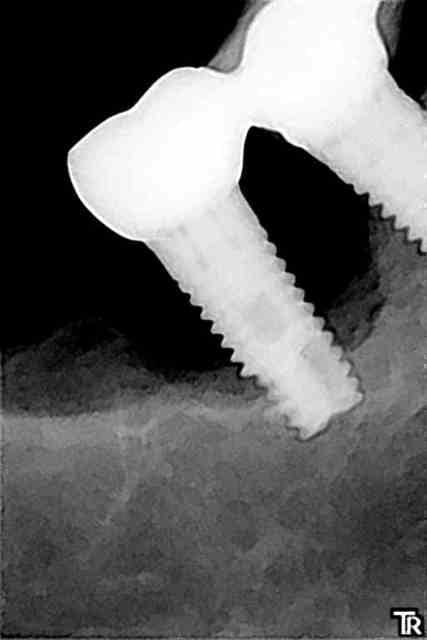

le "truc" que je comprends pas: pourquoi juste la 35, sachant que l'occlusion et la fonction sont OK, pas de problème d'adaptation de la prothèse, ni de présence de ciment...

j'en suis à me demander si c'est pas un abcès "paro" (je devrais dire périimplantaire) suite à une blessure avec un aliment (genre crustacés stars des fêtes de fin d'année)...

Comme ça , à brûle pourpoints je dirais que les appuis étant plus important à gauche qu'à droite + l'effet piston de 23 et 25 (sur 35) + l'environnement osseux de cette zone (de part et d'autre du trou mentonnier)... mais bon je ne suis pas implanto , ce n'est qu'un simple avis mécanique . Je me demande si l'occlusion générale n'y est pas pour qq chose .

Plan B: les points de contacts interproximaux sur 35 , forcés par l'effet piston de 23 et 25 .

points de contacts ok, vérifiés, zéro mobilité, occlusion ok, mouvements propulsion/latéralités ok...

ce que je ne comprends pas c'est pourquoi je n'ai pas de perte en lingual (c'est vrai que c'est pas facile à voir sur nonol, mais il n'y a pas de perte osseuse en lingual...çà forme une cuvette en forme de "croissant" avec point bas vestibulaire) ou du moins pas encore...

la cause mécanique pure, j'ai un peu de mal à y croire...mais bon, il peut y avoir un truc qui m'a échappé...